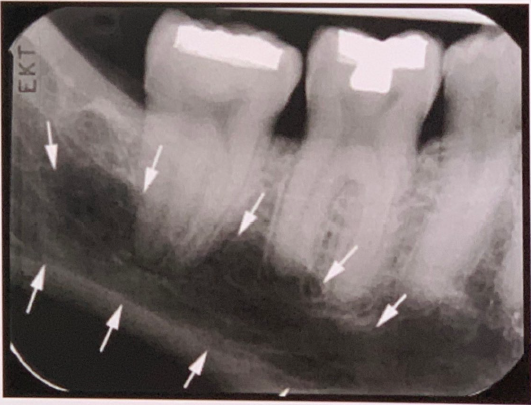

95. What is showing by red arrow?

External Oblique Ridge a continuation of the anterior border of the mandibular ramus. It follows an anteroinferior course lateral to the alveolar process.